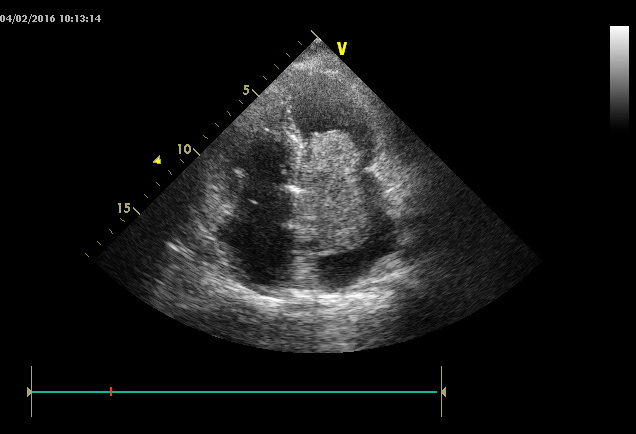

4. Рис.1 | |

| Тема | ||

| Тип | Прочее | |

Посмотреть

(57KB)